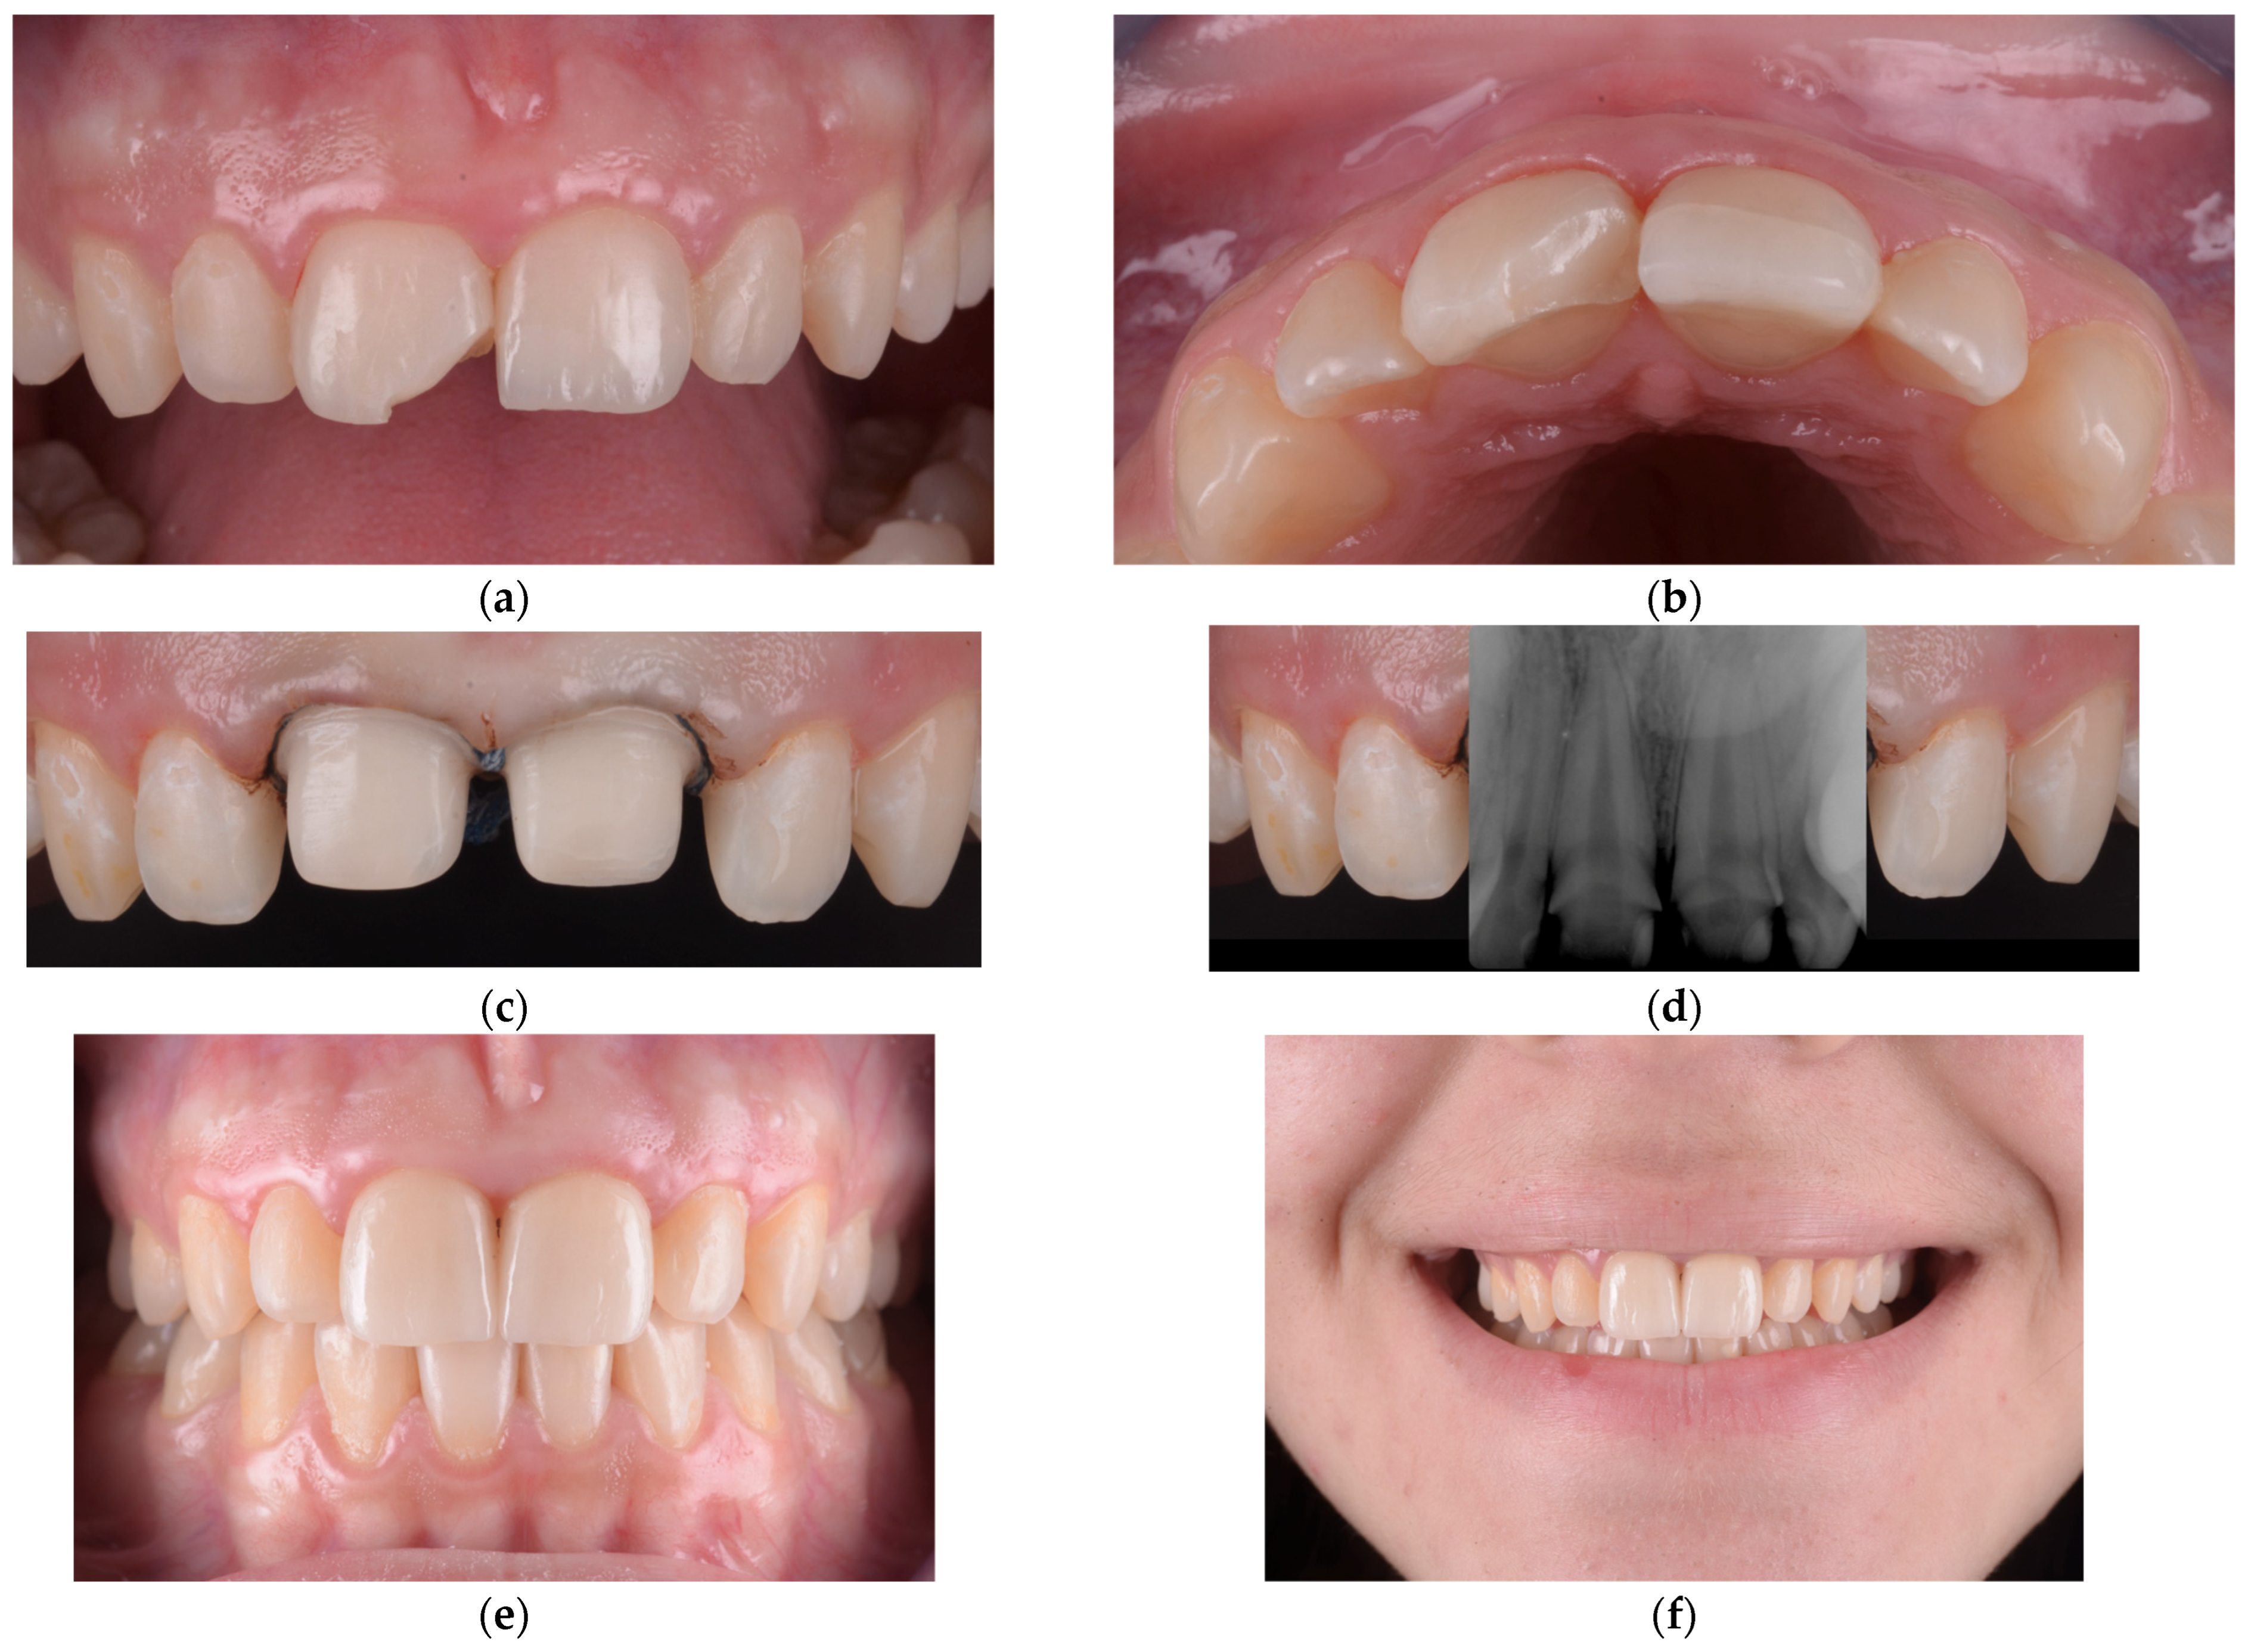

In our clinical experience, some feldspathic ceramic veneers failed over time, primarily due to chipping or fracture under functional load. In such cases, the affected teeth were prepared for lithium disilicate restorations, which offer superior mechanical resistance and better long-term performance in structurally compromised teeth. This approach mirrored our management of failed fragment reattachments, where lithium disilicate crowns were likewise used as a reliable restorative alternative. One such case is presented in Figure 6, illustrating the clinical workflow and the material adaptation following veneer failure.

Figure 6.

(a) Fracture of the feldspathic ceramic veneer affecting the incisal third of the maxillary left central incisor. (b) Occlusal view confirming the extent and morphology of the ceramic fracture. (c) Tooth preparations for lithium disilicate restorations, with retraction cords placed to avoid biological width violation. (d) Periapical radiograph illustrating the large pulp chamber volume and confirming that vitality was preserved following conservative preparation. (e) Intraoral frontal view of the lithium disilicate crowns after final cementation. (f) One-month recall showing a smile with color and morphology matching the adjacent teeth, demonstrating stable esthetic integration within the dental arch.